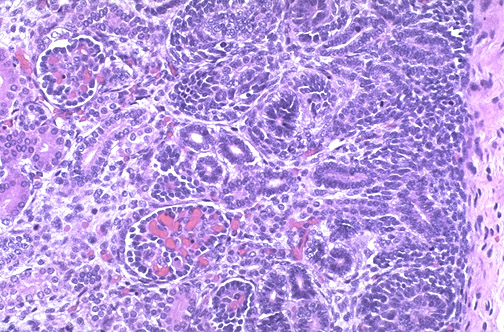

In the outer cortex of the fetal kidney below the capsule is the nephrogenic zone composed of primitive dark blue cells in which development of glomeruli and tubules is taking place.